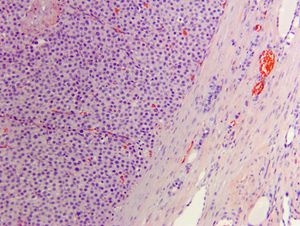

Canine thyroid carcinoma in 4-year-old American bulldog: Anatomic pathology perspective

Dr. Caitlin Brown provides the anatomic pathology perspective on this challenging oncology case.